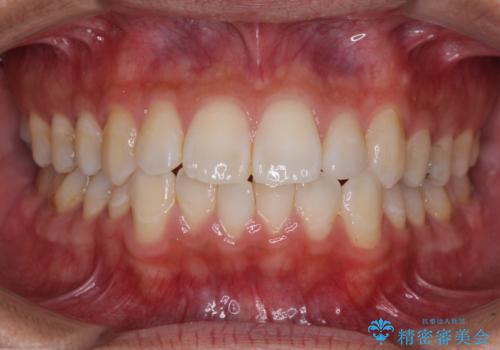

![[ インビザライン矯正 ] マウスピース矯正で治す、前歯のガタつきの症例 治療後](https://seimitsushinbi.jp/wp/wp-content/uploads/2022/02/IMG_1698-500x350.jpg?v=1644473356)